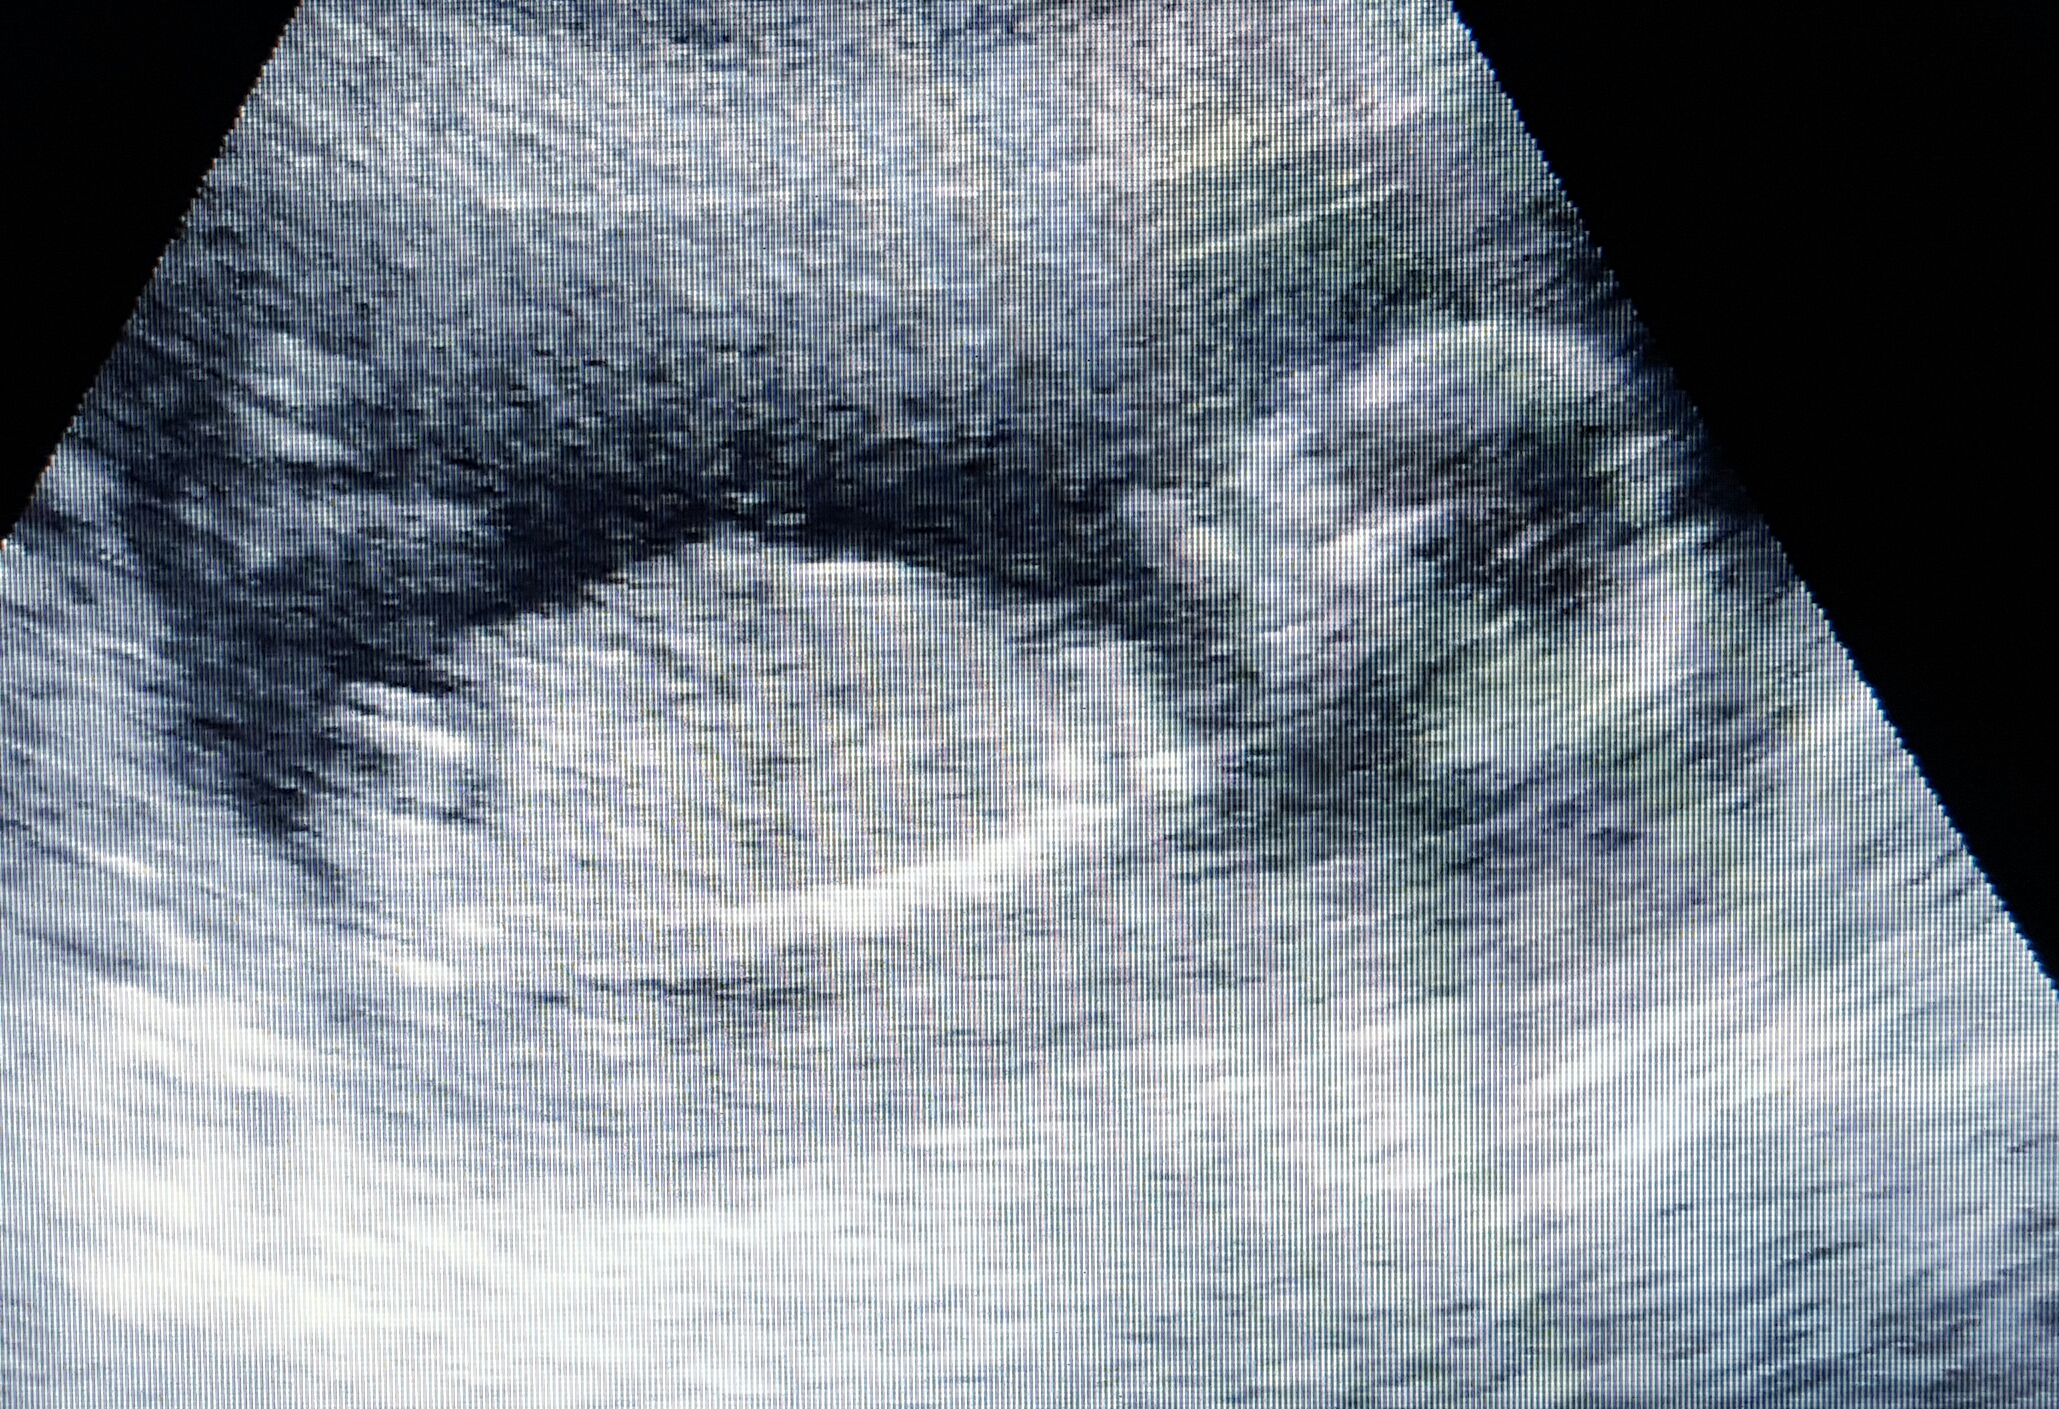

I posted this one on ingender and everyone guessed different to previous, what are your thoughts?

I have 3d gender reveal scan Monday when I'm 16 weeks, this photo is from 16 weeks opinions? And reasons?